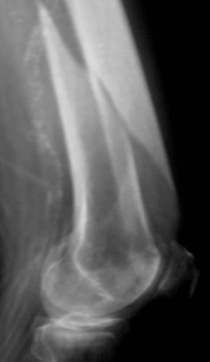

90-jährige Patientin mit distaler Oberschenkel-trümmerfraktur

postoperativer Befund nach geschlossener Nagelung

auch in der Seitaufnahme achsengerechte Stellung der Fraktur